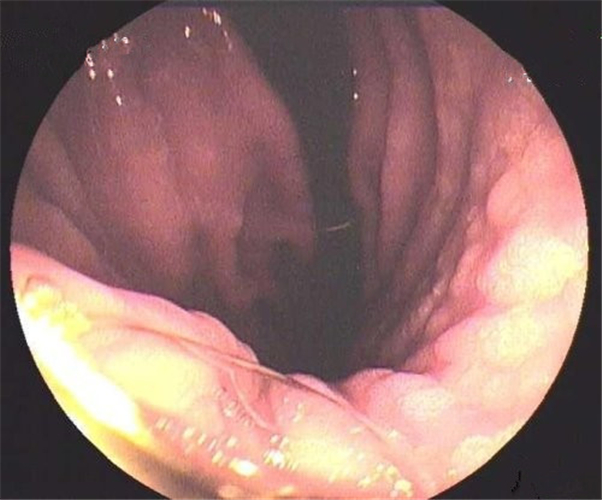

慢性胃炎

慢性胃炎的

成人慢性胃炎

淺表型慢性胃炎怕

淺表型慢性胃炎

輕型慢性胃炎

淺表型慢性胃炎發發

淺表型慢性胃炎好